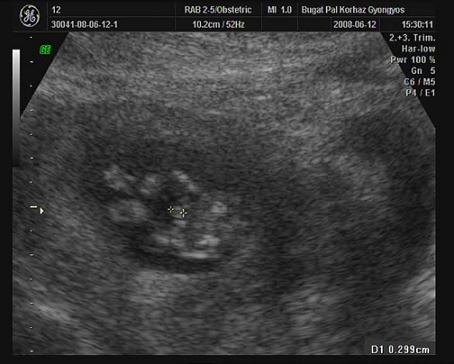

Rakok még két normál uh-s képet.

Itt mérik a kukit(remélhetöleg):

Kép

Kis ufó, szemböl, kezei meg a feje mellett:

A babának bizony ott a "3.lába"! PASIURALOM!!!!!!!!!!!!!!!